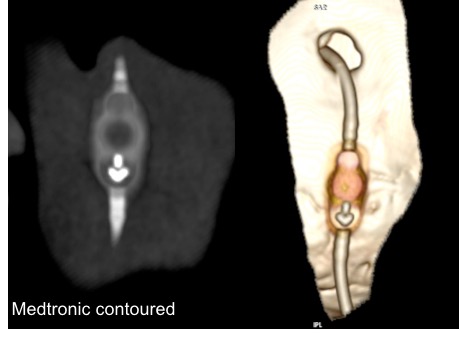

il existe un grand nombre de valves ; il n’est pas toujours aisé de les reconnaitre radiologiquement. voici la liste des plus courantes :

comment reconnaitre radiologiquement le type de valve ?